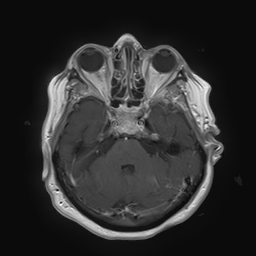

(a) Guide 𝑮𝑮\boldsymbol{G}

(b) Input 𝑰𝑰\boldsymbol{I}

(c) Guidance map 𝑴𝑴\boldsymbol{M}

(d) Prediction 𝑷𝑷\boldsymbol{P}

(e) Ground truth

(f) Guide 𝑮𝑮\boldsymbol{G}

(g) Input 𝑰𝑰\boldsymbol{I}

(h) Guidance map 𝑴𝑴\boldsymbol{M}

(i) Prediction 𝑷𝑷\boldsymbol{P}

(j) Ground truth

Figure 2: Inputs and outputs of the guided filtering pipeline based on the WDSR network. T1 & T2 MRI pairs (a)-(e) and CT & MRI projection images (f)-(j).